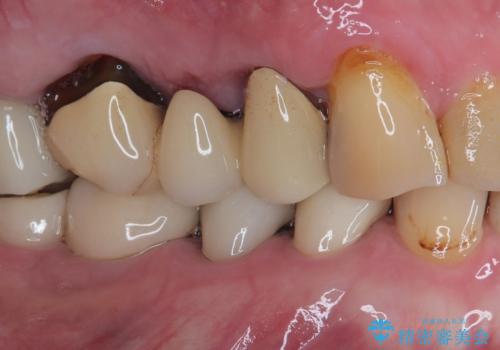

- 食事中に歯が欠けてしまったとのことで来院された患者様です。

以前詰めた材料が外れたか、歯が欠けたのかは分かりませんが、欠損している状態でした。

再度詰め物での処置を行うと引き続き欠けるリスクが高いため、高強度のフルジルコニアクラウンにて補綴治療を行うこととしました。